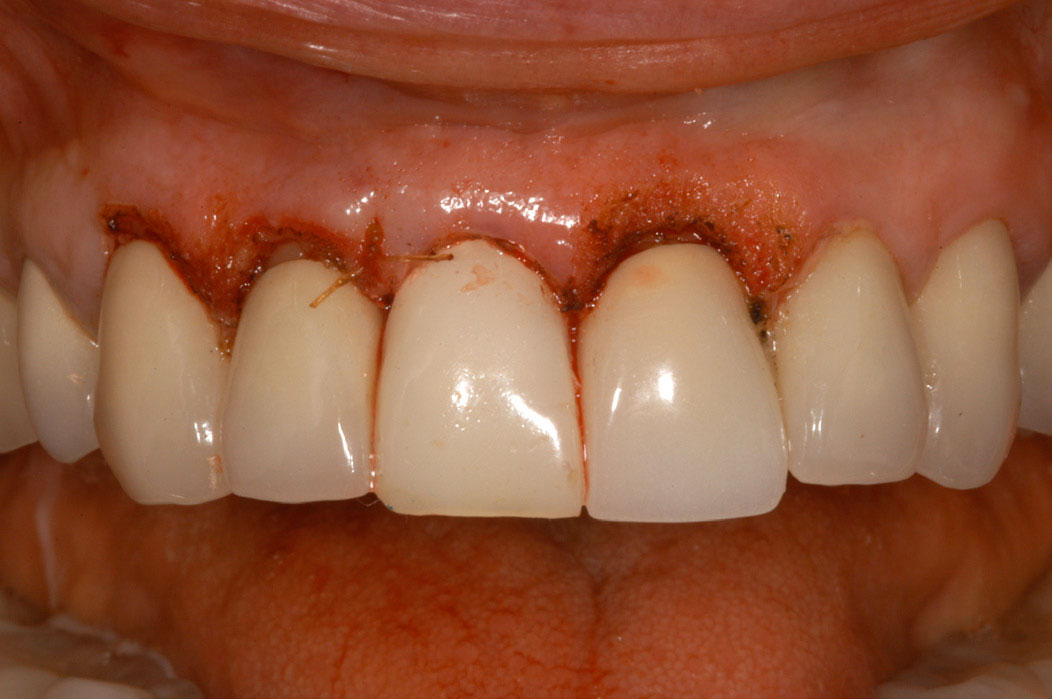

Figure 15 – Extraction of anterior tooth No. 8 without detaching the gingiva.

Figure 15

Figure 16 – Extracted tooth with the root canal material (gutta percha) extending from the apex

Figure 16

Figure 17– A zircon (white) abutment was attached immediately after extraction and implant placement.

Figure 17

Figure 18 – Immediate placement of temporary crown over the abutment; laser crown lengthening was performed on the adjacent teeth to improve gingival symmetry

Figure 18

Figure 19 – Four months after surgery with temporary crown over the implant at No. 8.

Figure 19